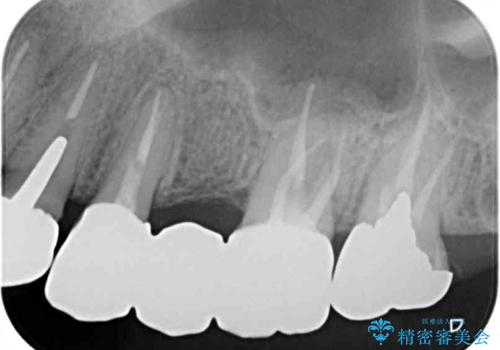

- 全顎的に銀歯が多く、その中でも1番目立って気になる上顎のブリッジをセラミックに替えたいとのことで来院された患者様です。

銀歯の適合が悪く、土台の歯に虫歯多く残っていたので、虫歯除去とファイバーコアによる土台植立を行い、フルジルコニア製ブリッジを装着することとしました。